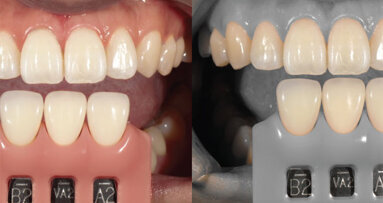

Fig. 1: Implant planning and surgical guide design. (All images: Dr Neeraj Surathu)

Phase 1: Implant planning and guided surgery

A well-placed implant is critical for a successful restoration because implant positioning affects the thickness of the restoration, location of the screw access hole, emergence profile and aesthetics. The digital workflow begins with meticulous implant planning using advanced software to design a surgical guide for precise implant placement (Fig. 1).